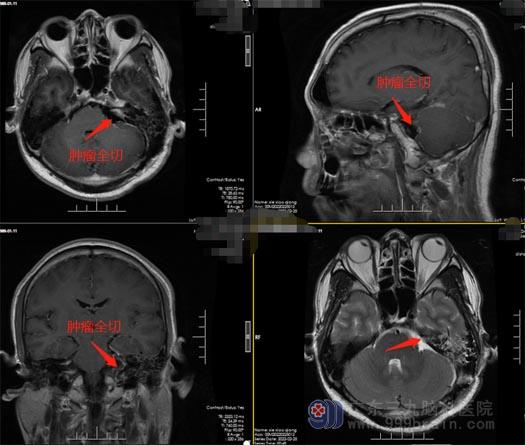

谢先生的爱人经多方打听,得知广东三九脑科医院神经外五科王国良团队是手术经验非常丰富的脑科团队,在广东三九脑科医院完善各项术前检查和准备工作后,由王国良主任主刀,在全麻下行“左侧桥小脑角听神经瘤切除术”,术中全切肿瘤,听神经、面神经保护完好,手术顺利结束。

▲术后